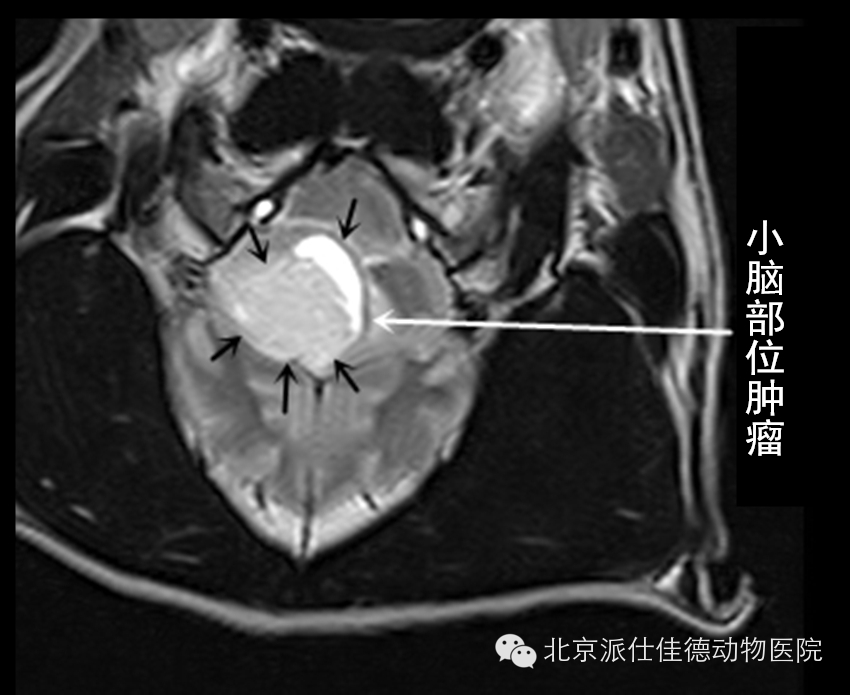

15.有些动物表现为转圈,突然四肢共济失调,走路打晃,经诊断发现是脑部肿瘤压迫引发。

16.有些动物表现为突发癫痫,不停的抽搐,经核磁共振扫描发现脑积水、脑炎、脑肿瘤等等。